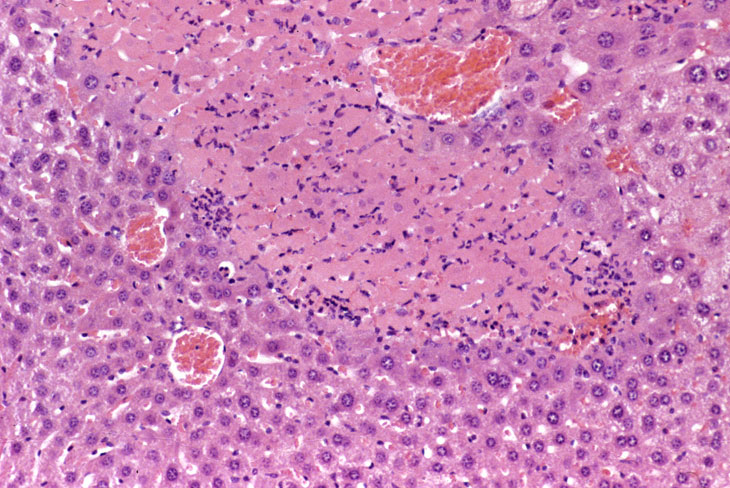

Coagulation necrosis is characterized by distinct eosinophilic cytoplasm with pyknotic or absent nuclei. Infarction of hepatic lobes is a form of coagulation necrosis.

Focal coagulation necrosis.